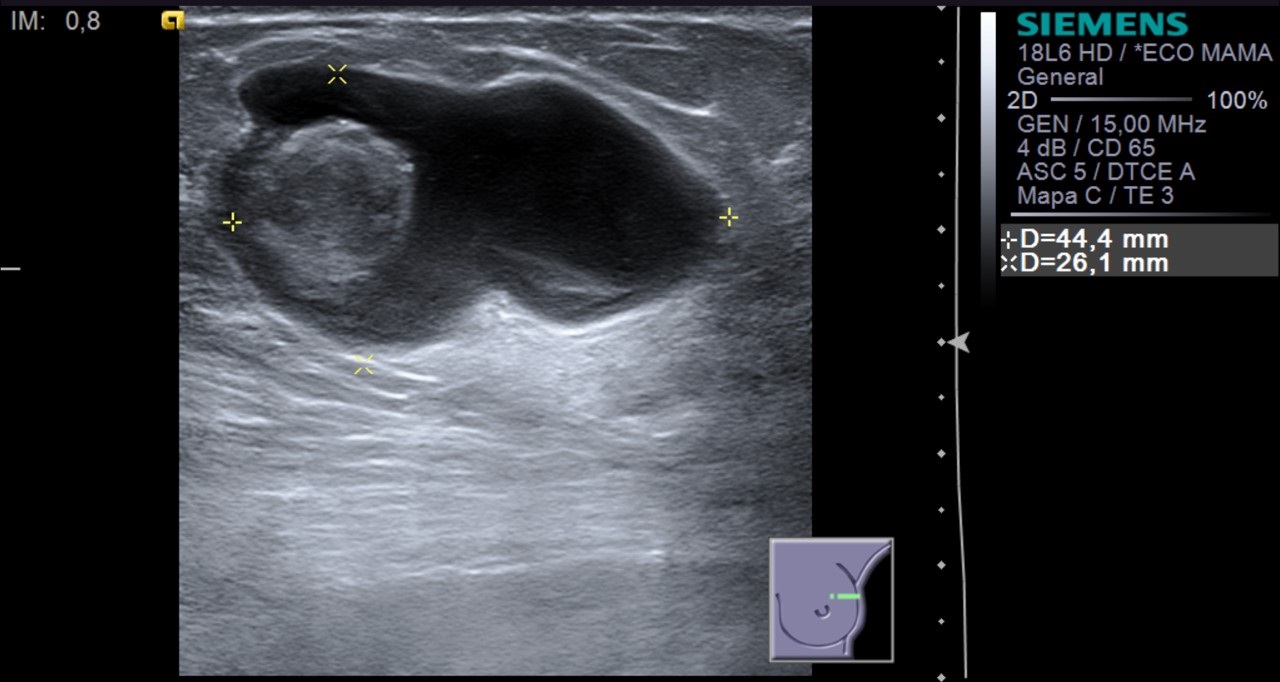

La ecografía es una prueba diagnóstica indispensable en la valoración de la patología mamaria. Si bien en las pacientes sintomáticas alrededor de los 40 años no es la primera prueba de elección, la ecografía complementa a la mamografía. En nuestro caso nos va a permitir valorar la naturaleza sólida o quística de las lesiones.

¿Qué hallazgo radiológico se puede identificar en la ecografía?